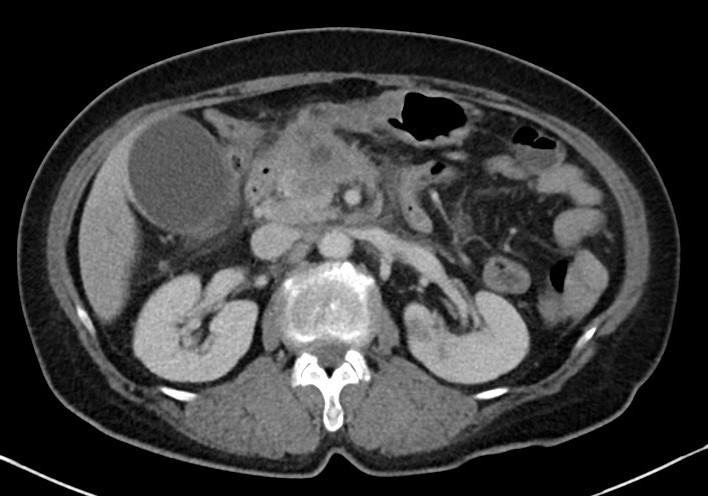

66세 남자가 3일 전부터 얼굴이 노래지고 소변색이 진해져서 응급실에 왔다. 최근 1개월간 몸무게가 9 kg 정도 빠졌다고 한다. 혈압 130/80 mmHg, 맥박 96회/분, 호흡 20회/분, 체온 36.3 ℃이다. 온몸과 공막이 노랗다. 배에 압통이나 반동압통은 없다. 이전 수술력은 없다고 한다. 혈액검사 결과는 다음과 같다. 복부 컴퓨터단층촬영 사진이다. 조치는?

CT: Distal CBD mass, upstream biliary dilatation, GB dilatation, multiple low-attenuating hepatic lesions

Imp: 원위부 담관암(distal cholangiocarcinoma)

임상양상 및 CT 소견으로 보아 distal cholangiocarcinoma가 강력히 의심되며, 현재 정체된 담즙을 급하게 배액하기 위한 ERCP가 필요하다.

• CT상 distal CBD에 종양이 확인되며, 이보다 upstream하게 CBD와 GB가 늘어난 것이 보인다. 또한 간에 저음영 nodule이 몇 개 보이는데, 이는 distal cholangiocarcinoma의 간 전이를 시사한다.

• 따라서 본 환자의 cholangiocarcinoma는 unresectable할 가능성이 매우 높으며, 따라서 근치적 치료보다는 현재 가장 큰 문제인 biliary obstruction을 해소하기 위한 완화적 치료가 필요하다. 따라서 내시경역행담관조영(endoscopic retrograde cholangiopancreatography, ERCP)을 통해 stent 삽입 등을 이용한 배액을 시도해야 한다.